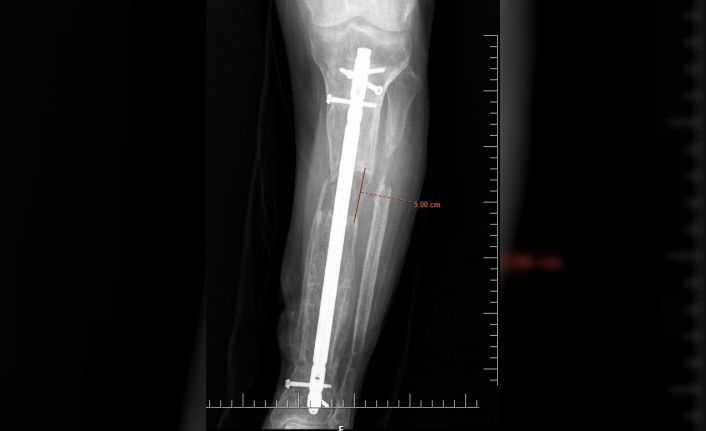

İsmi açıklanmayan bir erkek hasta, 5 yıl önce iş kazası geçirdi. Hastanın kaval kemiğinde parçalı kırıklar oluşması sonucu bacağı diğerine kıyasla kısaldı. 5 yıl boyunca aksayarak yürümek zorunda kalan hasta, Elbistan Devlet Hastanesi’ne başvurdu. Ortopedi servisinde Ortopedist Op. Dr. Ali Canbay ve Op. Dr. Serdar Karaman tarafından tetkikleri yapılan hastaya, boy (kemik) uzatma operasyonu yapılması kararlaştırıldı. Hastanın bacağına, ilk ameliyatında kısa olan kemiği günde 1 mm uzatma olacak şekilde bir sistem kuruldu. Başarılı geçen operasyon sonrasında kurulan sistem sayesinde 5 cm uzama ve yıllardır kaynamayan kemikte kaynama elde edildi. Son olarak dışarıdan uygulanan bu sistem çıkarıldı ve uzamanın kontrol altına alınması için çivi denilen işlem uygulandı. Hasta, tüm bu işlemlerin akabinde aksamadan yürümeye başlayarak eski sağlığına kavuştu.

Operasyonla ilgili Elbistan Devlet Hastanesi’nden yapılan açıklamada; “İş kazası nedeniyle beş yıl önce kaval kemiğinde parçalı kırığı olan ve kırık olan bacağında diğer bacağına kıyasla kısalığı devam eden hastamıza, Elbistan Devlet Hastanesi’nde Ortopedist Op. Dr. Ali Canbay ve Op. Dr. Serdar Karaman’ın birlikte yaptıkları iki operasyon sonucu hasta eski sağlığına kavuşmuştur. İlk ameliyatında kısa olan kemiği günde bir milimetre uzatma olacak şekilde kurulan sistem ile 5 cm uzama ve yıllardır bir türlü kaynamayan kemikte kaynama elde edilmiştir. Son olarak dışarıdan uygulanan sistem çıkarılıp hastanın konforlu hayatına dönmesi için çivi denilen işlem ile mevcut uzamanın koruma altına alınıp hastanın tekrar aksamadan yürümesi sağlanmıştır” denildi.